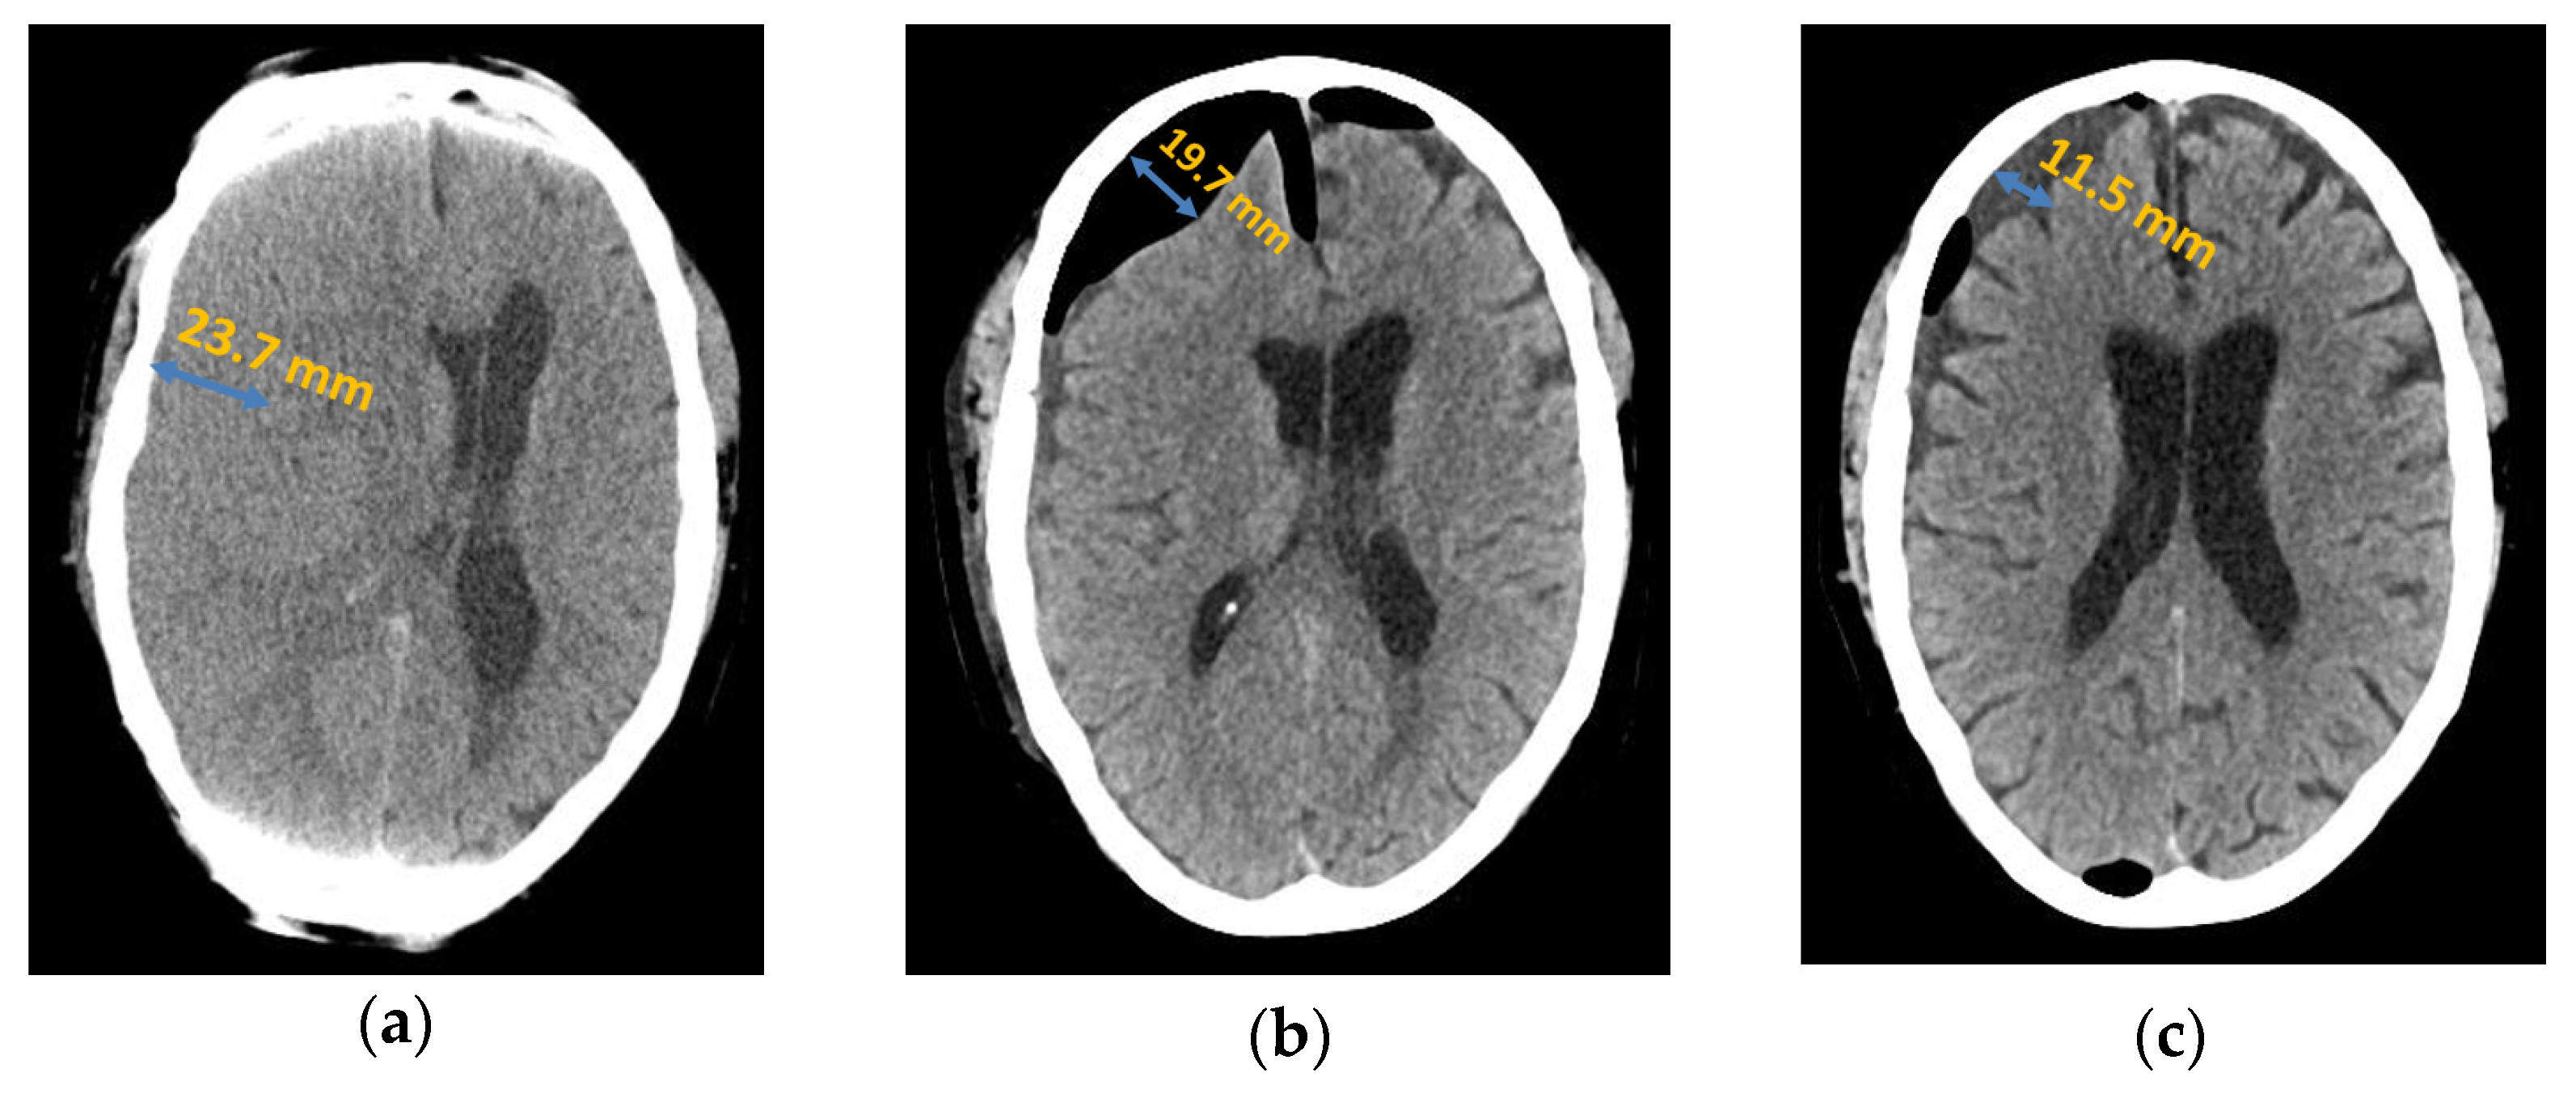

The total patient population consisted of 90 patients with chronic subdural haematoma. In 29 patients (32%), no associated trauma could be identified. In 61 patients (68%), trauma in the weeks prior to diagnosis was identified as the cause of the subdural haematoma, including falls in 34 patients (38%), traffic accidents in 5 patients (6%), and minor trauma (e.g., minor head trauma to the edge of the door without a fall) in 22 patients (24%). Of the total patient population, 60 patients (67%) did not develop a recurrence and 30 patients (33%) had a recurrence. In 80% (n = 24) of these 30 cases, one recurrent haemorrhage required treatment, in 16.67% (n = 5) there was a second recurrence, and in 3.33% (n = 1), there was a third recurrence requiring treatment; see Figure 1.

Figure 1.

Axial computed tomography of chronic subdural haematoma: (a) preoperative presentation; (b) postoperative subdural air accumulation; (c) recurrence of chronic subdural haematoma.